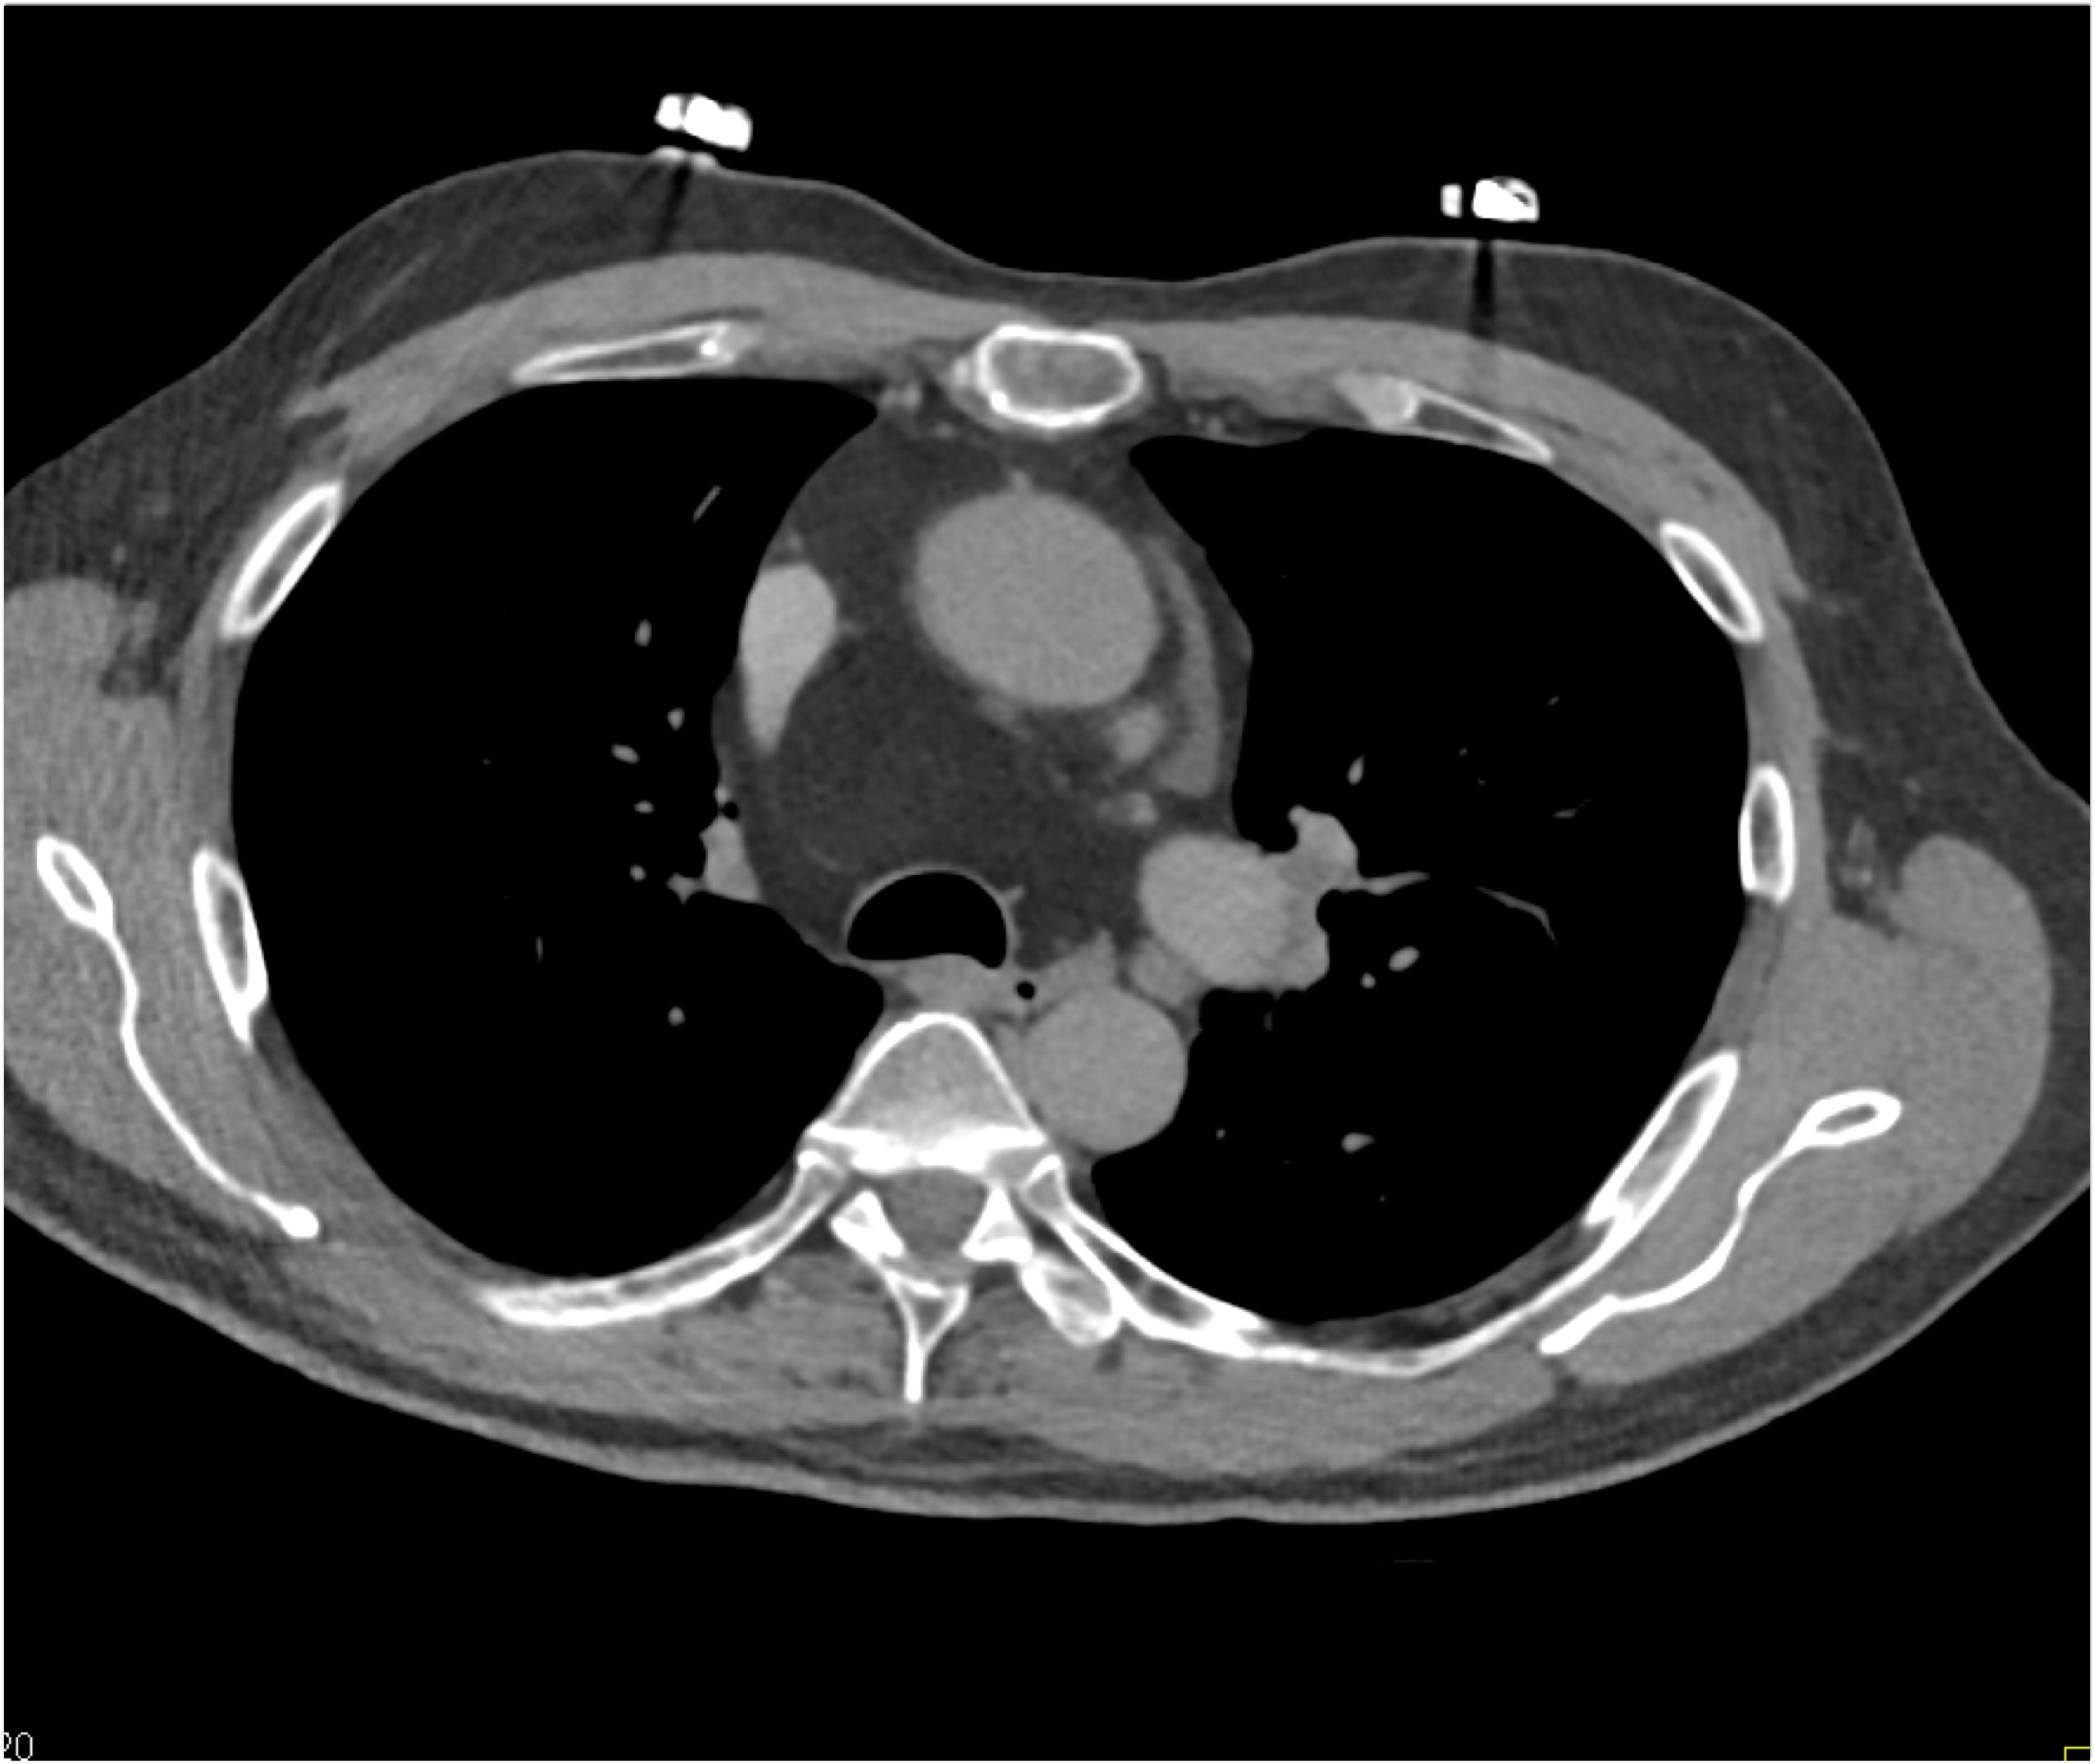

8) In this patient with mediastinal widening on CXR the best diagnosis is?

lymphoma

germ cell tumor

lung cancer

teratoma